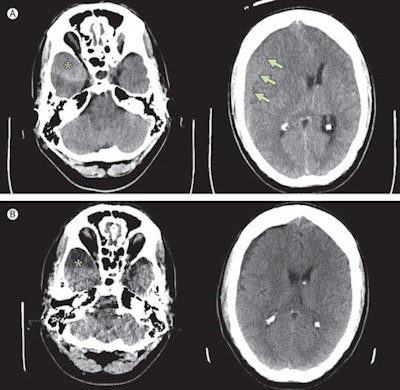

A: Preoperative CT scan shows chronic subdural hematoma (maximum width 20 mm, arrows) with midline shift and a clot (asterisk) at the tip of the right temporal lobe. B: Postoperative scan shows resolution of the subdural hematoma and an arachnoid cyst (asterisk) at the tip of the temporal lobe. The scans were performed without contrast using a system from GE Healthcare. Copyright © Institute of Diagnostic and Interventional Neuroradiology, Hannover Medical School.A cranial CT scan confirmed the man had a chronic subdural hematoma on the right side of his brain. Surgeons removed the hematoma through a burr hole and used closed system subdural drainage for six days after surgery. His headache subsided and his last examination two months later revealed he was well (Lancet, 5 July 2014, Vol. 384, pp. 102).

The Hannover case illustrates the impact of headbanging on the development of subdural hematoma, according to Islamian. The patient displayed an arachnoid cyst in the middle cranial fossa; these cysts usually are detected in asymptomatic patients evaluated for unrelated symptoms, and, in a minority of cases, they become symptomatic by, for example, traumatic intracystic or subdural hemorrhage caused by rupture of bridging veins or unsupported veins surrounding the cyst.